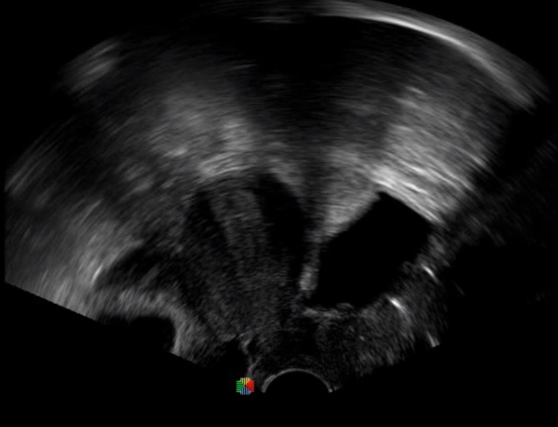

胎移植臨床圖

多數(shù)的生殖科醫(yī)生對于受精卵的植入采用憑經(jīng)驗操作或是使用傳統(tǒng)腔內(nèi)探頭引導(dǎo),同樣存在手術(shù)空間小、受精卵放置位置不確定等風(fēng)險。專業(yè)的宮腔專用探頭,配合專用的窺器使用,為醫(yī)生提供最大的手術(shù)視野。